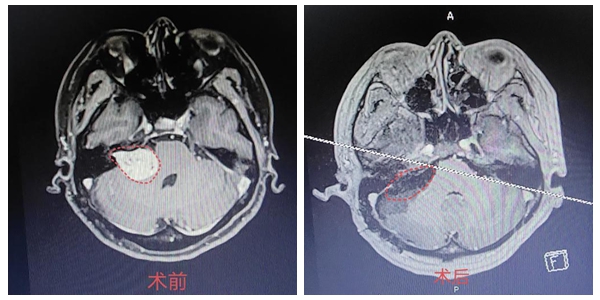

在对患者病情进行全面评估,确定个性化手术方案后,袁贤瑞教授团队在全麻下为患者行开颅探查听神经瘤切除术+脑脊液漏修补术。全麻插管后,患者取左侧俯卧位,沿原切口切开头皮,显微镜下弧形剪开硬膜,见硬脑膜与小脑紧密黏连,剥离硬脑膜,见病变位于右侧桥小脑角区,约3.8cm×3.5cm×3.0cm大小,质地中等,血供较丰富,实性,肿瘤与小脑、脑干紧密黏连,灰黄色,内听道扩大,部分肿瘤伸入内听道内,极难剥离。历时6个小时,最终实现肿瘤全切,完美保留面神经功能。术后安返病房,在医护团队精心治疗下,最终康复出院。

袁贤瑞教授术后表示:“考虑患者已经历过一次手术,肿瘤变得非常坚硬,面神经被推挤至肿瘤腹侧,薄如纸状,与肿瘤粘连紧密,后组颅神经位于肿瘤下极,所以我们采取了先行瘤内减压,再确认面神经脑干端,依次分离肿瘤下极、上极、内侧面,分离肿瘤与面听神经粘连,最后磨开内听道后壁,将内听道内肿瘤全部切除。整个手术复杂,难度很高,具有很重要的学习探讨意义”。